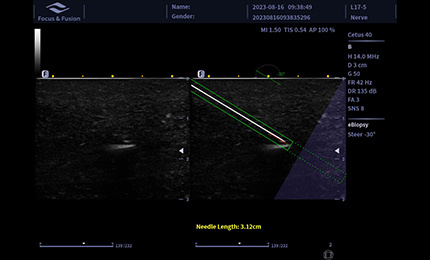

Obraz igły punkcyjnej jest wzmocniony przez odchylenie wiązki akustycznej, obejmujące wzmocnienie igły, renderowanie czerwonego końca igły, wirtualny przebieg igły oraz linię skali, wspierające automatyczne sterowanie.